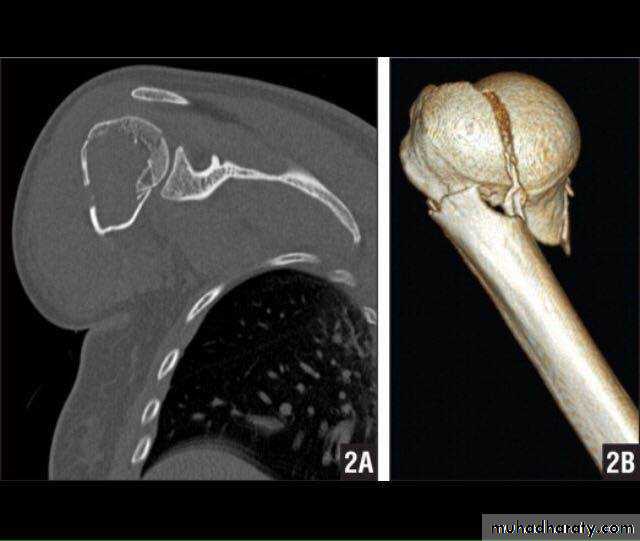

CT

20

3D CT

29

34